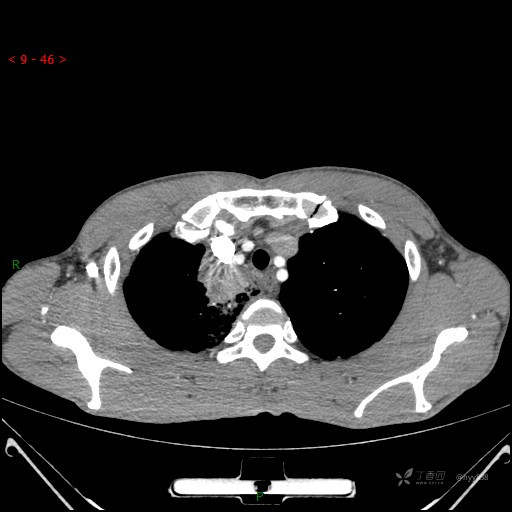

增强动脉期